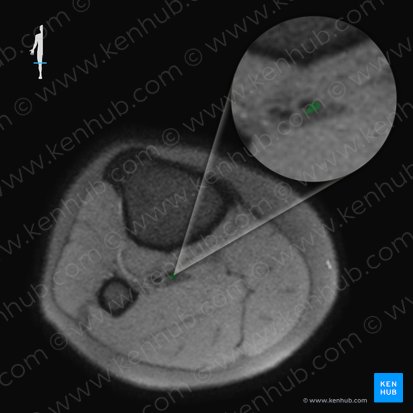

Through the leg, the posterior tibial veins follow the posterior tibial artery and traverse the quadrangular interval bounded by the transverse intermuscular septum (posteriorly), flexor digitorum longus (medially), flexor hallucis longus (laterally), and tibialis posterior (anteriorly). The posterior tibial veins end at the distal margin of the popliteus muscle, where they merge with the anterior tibial veins and form the popliteal vein.